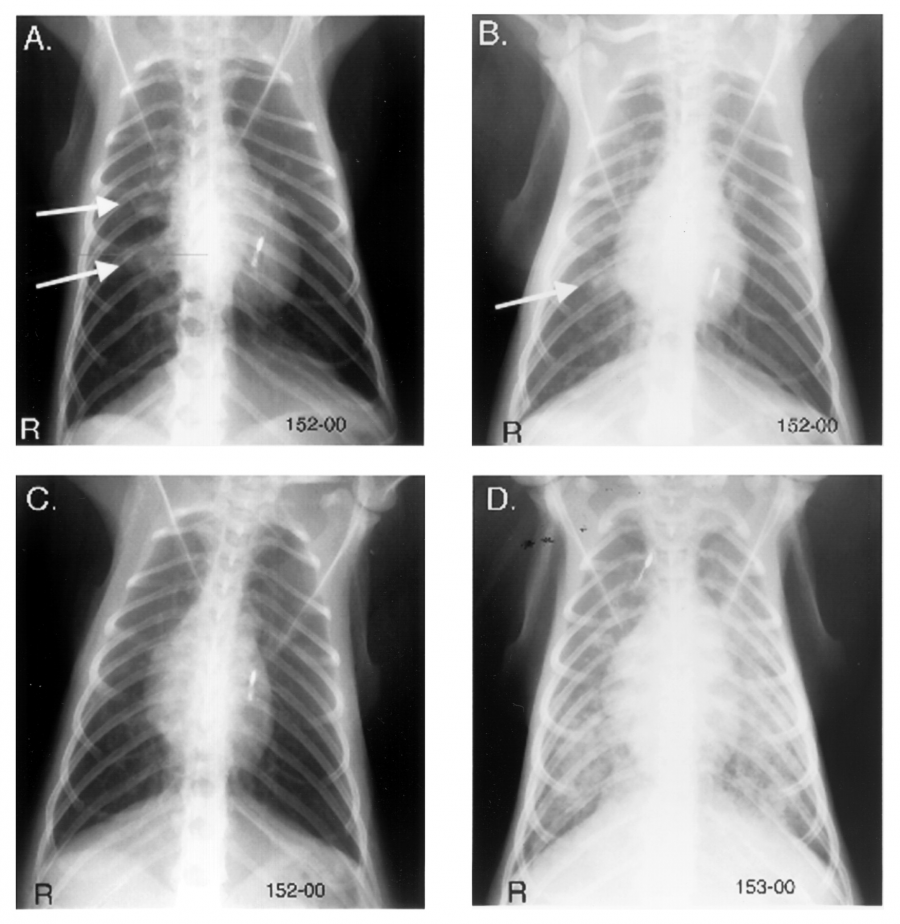

2. X光影像

X光影像在人的结核筛查中是一种常用的方法,在NHP案例中,较不容易出现钙化灶,并非是一种理想的筛查方法,但是也可以作为辅助检查方法应用。